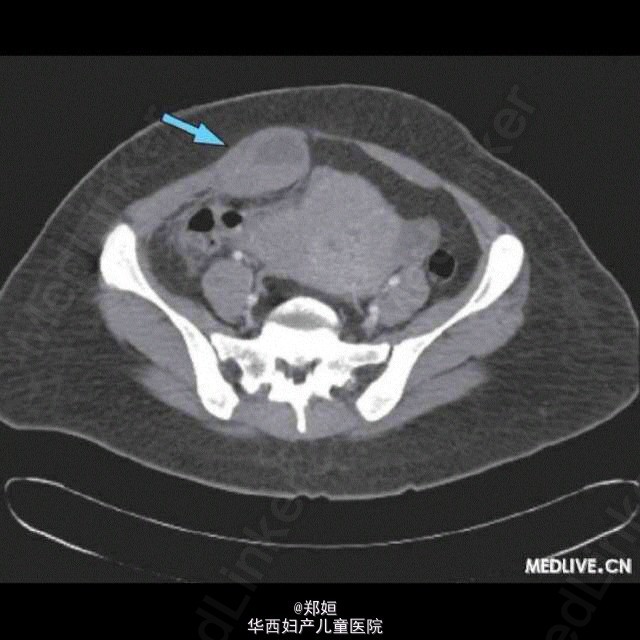

病历资料:女,37岁,右髂窝疼痛3天, 查体:右髂窝部压痛,在骨盆和下腹部可触及一直径为16 cm的肿块。患者无宫颈刺激, 孕检结果为阴性。入院时,血红蛋白105 g/L,白细 胞计数4.93×109/L。有血小板减少症(108×109/L),但在13 d前患者血小板计数还在正常范围内,凝血酶原时间延长至15.1 s。 腹部超声和CT均显示一个巨大球状子宫,子宫壁肌层回声粗糙,提示为子宫内膜异位症。但骨盆-腹部的肿块可能主要是由腹直肌鞘内的机化 血肿引起的。 血清学检测表明患者近期有登革热病毒的感染,患者IgM抗体阳性,IgG抗体阴性。 CT还偶然发现了一个位于左侧股静脉的血栓,多普勒超声显示左侧腿部的广泛性深静脉血栓。血栓形成倾向筛查试验显示蛋白S、蛋白C及抗 凝血酶Ⅲ浓度正常。 诊断:登革热病毒感染后导致的出血 治疗:停用口服避孕药、安置下腔静脉滤过器,推迟5 d进行抗凝治疗以稳定血肿。患者血小板计数恢复正常后,开始终身服用华法林预防性 治疗。采用保守方法治疗血肿,未行引流。 结局:6个月后,患者腹直肌鞘内血肿完全消失。 http://case.medlive.cn/obgyn/case-article/show-40304_207.html